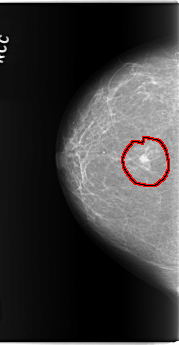

C_0143_1.RIGHT_MLO

FILE: C_0143_1.RIGHT_MLO.OVERLAY

TOTAL_ABNORMALITIES 1

ABNORMALITY 1

LESION_TYPE MASS SHAPE IRREGULAR MARGINS ILL_DEFINED

ASSESSMENT 5

SUBTLETY 5

PATHOLOGY MALIGNANT

TOTAL_OUTLINES 1

BOUNDARY